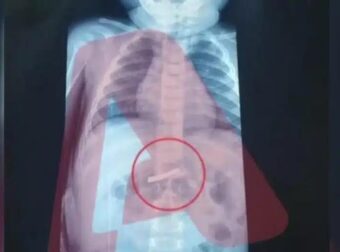

Στο νοσοκομείο Παίδων 3χρονο αγόρι – Τι σoκaριστικό κατάπιε